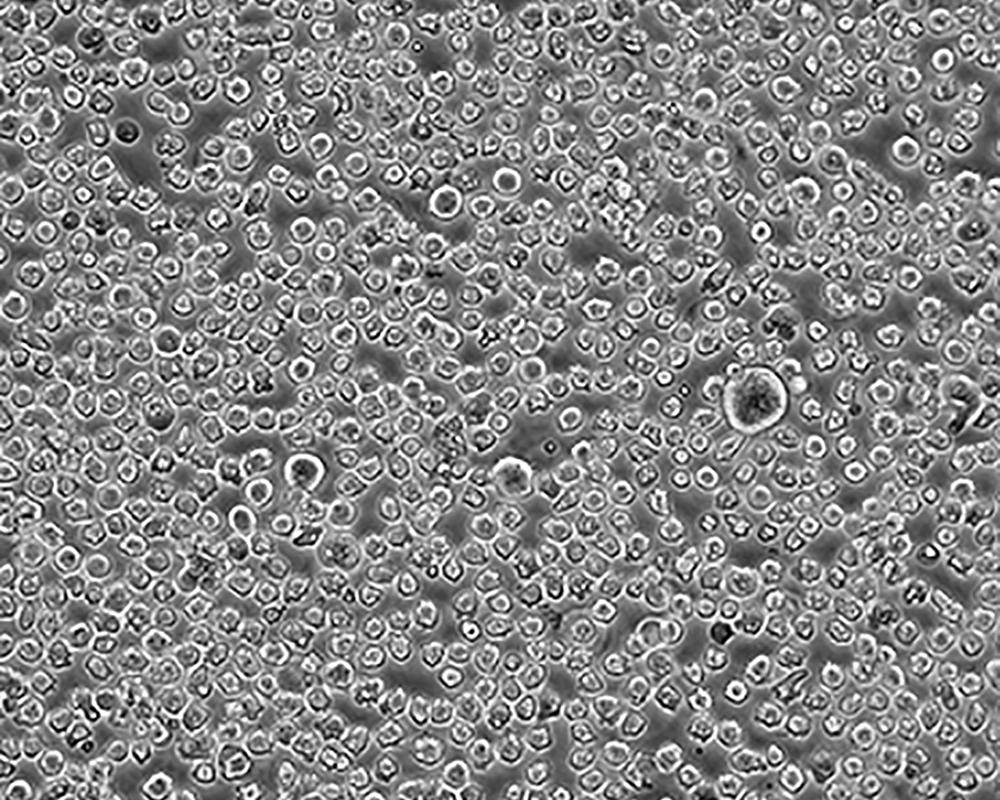

生長特性 suspension

形態特征 lymphoblast

傳代方法 1:2-1:4

細胞描述 The cell population has been characterized as highly undifferentiated and of the granulocytic series. Studies conducted by Anderson, et al. , on the surface membrane properties led to the conclusion that the K-562 was a human erythroleukemia line. K-562 blasts are multipotential, hematopoietic malignant cells that spontaneously differentiate into recognizable progenitors of the erythrocytic, granulocytic and monocytic series. The effect of inducers on sublines derived from the original K-562 cell line have been reviewed by Koeffler and Golde. Karyological studies on various K- 562 sublines have been classified into three groups(A,B,C) by Dimery, et al. The strain obtained by the ATCC most closely resembles the B population. Occurrence of the Philadelphia chromosome, however, was of much lower frequency; none detected in 15 metaphases examined. The line is EBNA negative.